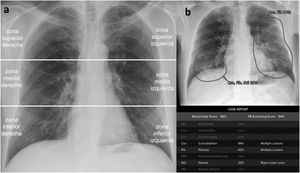

Probabilidad de afectación en cada zona pulmonar. Para ello, se analizaron las radiografías de tórax tras dividir la imagen en 6 zonas pulmonares (fig. 1).

Concordancias con el estándar de referencia en la primera, segunda y tercera evaluacionesPara «probabilidad de neumonía COVID-19» con radiografía (fig. 6) se obtuvieron 20 valores K tras agrupar el valor K de cada lector para la primera y la segunda evaluación. Como en el caso anterior, las concordancias de todos los lectores con el estándar de referencia en la primera y la segunda evaluaciones sin IA fueron predominantemente buenas (14/20 [70%]) frente a concordancias excelentes (2/20 [10%]) y moderadas (4/20 [20%]). Con la IA, las concordancias fueron buenas (9/10 [90%]) excepto una moderada (1/10 [10%]).

Concordancia para «probabilidad de neumonía COVID-19 con radiografía» entre cada lector y el estándar de referencia.

Para cada evaluación, el coeficiente kappa corresponde al centro de la barra y sus intervalos de confianza del 95% a los límites de la barra.

Para la evaluación con inteligencia artificial (IA) se muestra el valor K en la etiqueta central, y el porcentaje de mejora (+) o empeoramiento (−) o ningún cambio (/) de la IA en comparación con el valor más alto de la primera y la segunda evaluación en la etiqueta superior; no se ha considerado ningún cambio cuando la IA generó un valor intermedio entre la primera y la segunda evaluación del lector.

IA: inteligencia artificial; EM4-1: estudiante de medicina de cuarto año número 1; EM4-2: estudiante de medicina de cuarto año número 2; EM5-1: estudiante de medicina de quinto año número 1; EM5-2: estudiante de medicina de quinto año número 2; EM6-1: estudiante de medicina de sexto año número 1; EM6-2: estudiante de medicina de sexto año número 2; RR2: residente de radiología de segundo año; RR3: residente de radiología de tercer año; RE1: radiólogo experto número 1; RE2: radiólogo experto número 2.